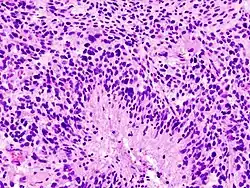

Gliomas malignos

Son los tumores cerebrales primarios más frecuentes y agresivos. Causan globalmente un 2 por ciento de las muertes por cáncer.[20] Los tres tipos histopatológicos más frecuentes son el glioblastoma multiforme, el astrocitoma anaplásico y el oligodendroglioma anaplásico. Estos tumores poseen una alta tasa de recidiva local tras tratamiento quirúrgico, progresando localmente, lo que finalmente termina causando la muerte del paciente. Se diseminan principalmente a través de la sustancia blanca o por vía líquido cefalorraquídeo. A diferencia del resto de las neoplasias malignas avanzadas, éstas no dan metástasis a distancia.

Glioblastoma multiforme: Constituye la forma más agresiva de los astrocitomas (tumor grado IV-OMS). Tradicionalmente se admitía que presentaba una supervivencia media, a los dos años, de aproximadamente 10 por ciento.[21] El tratamiento requiere un abordaje multidisciplinar que incluye cirugía, radioterapia y quimioterapia. Con uno de estos protocolos de tratamiento, el protocolo de Stupp[22] se ha alcanzado recientemente una supervivencia del 25 % y aún más en los casos en los que se consiguió una extirpación completa. El ideal es que en el tratamiento participen especialistas en neurocirugía, neurología y oncología.[23] Aunque el pronóstico es malo se han conseguido avances en los últimos años. Por ejemplo, la utilización de un producto (5-aminolevulinico) consigue colorear el tumor bajo luz fluorescente y mejorar la extirpación.[24] Es recomendable impulsar la participación en ensayos clínicos para buscar nuevos tratamientos,[25] se continúan buscando nuevos tratamientos con fármacos, inmunoterapia y virus oncolíticos.